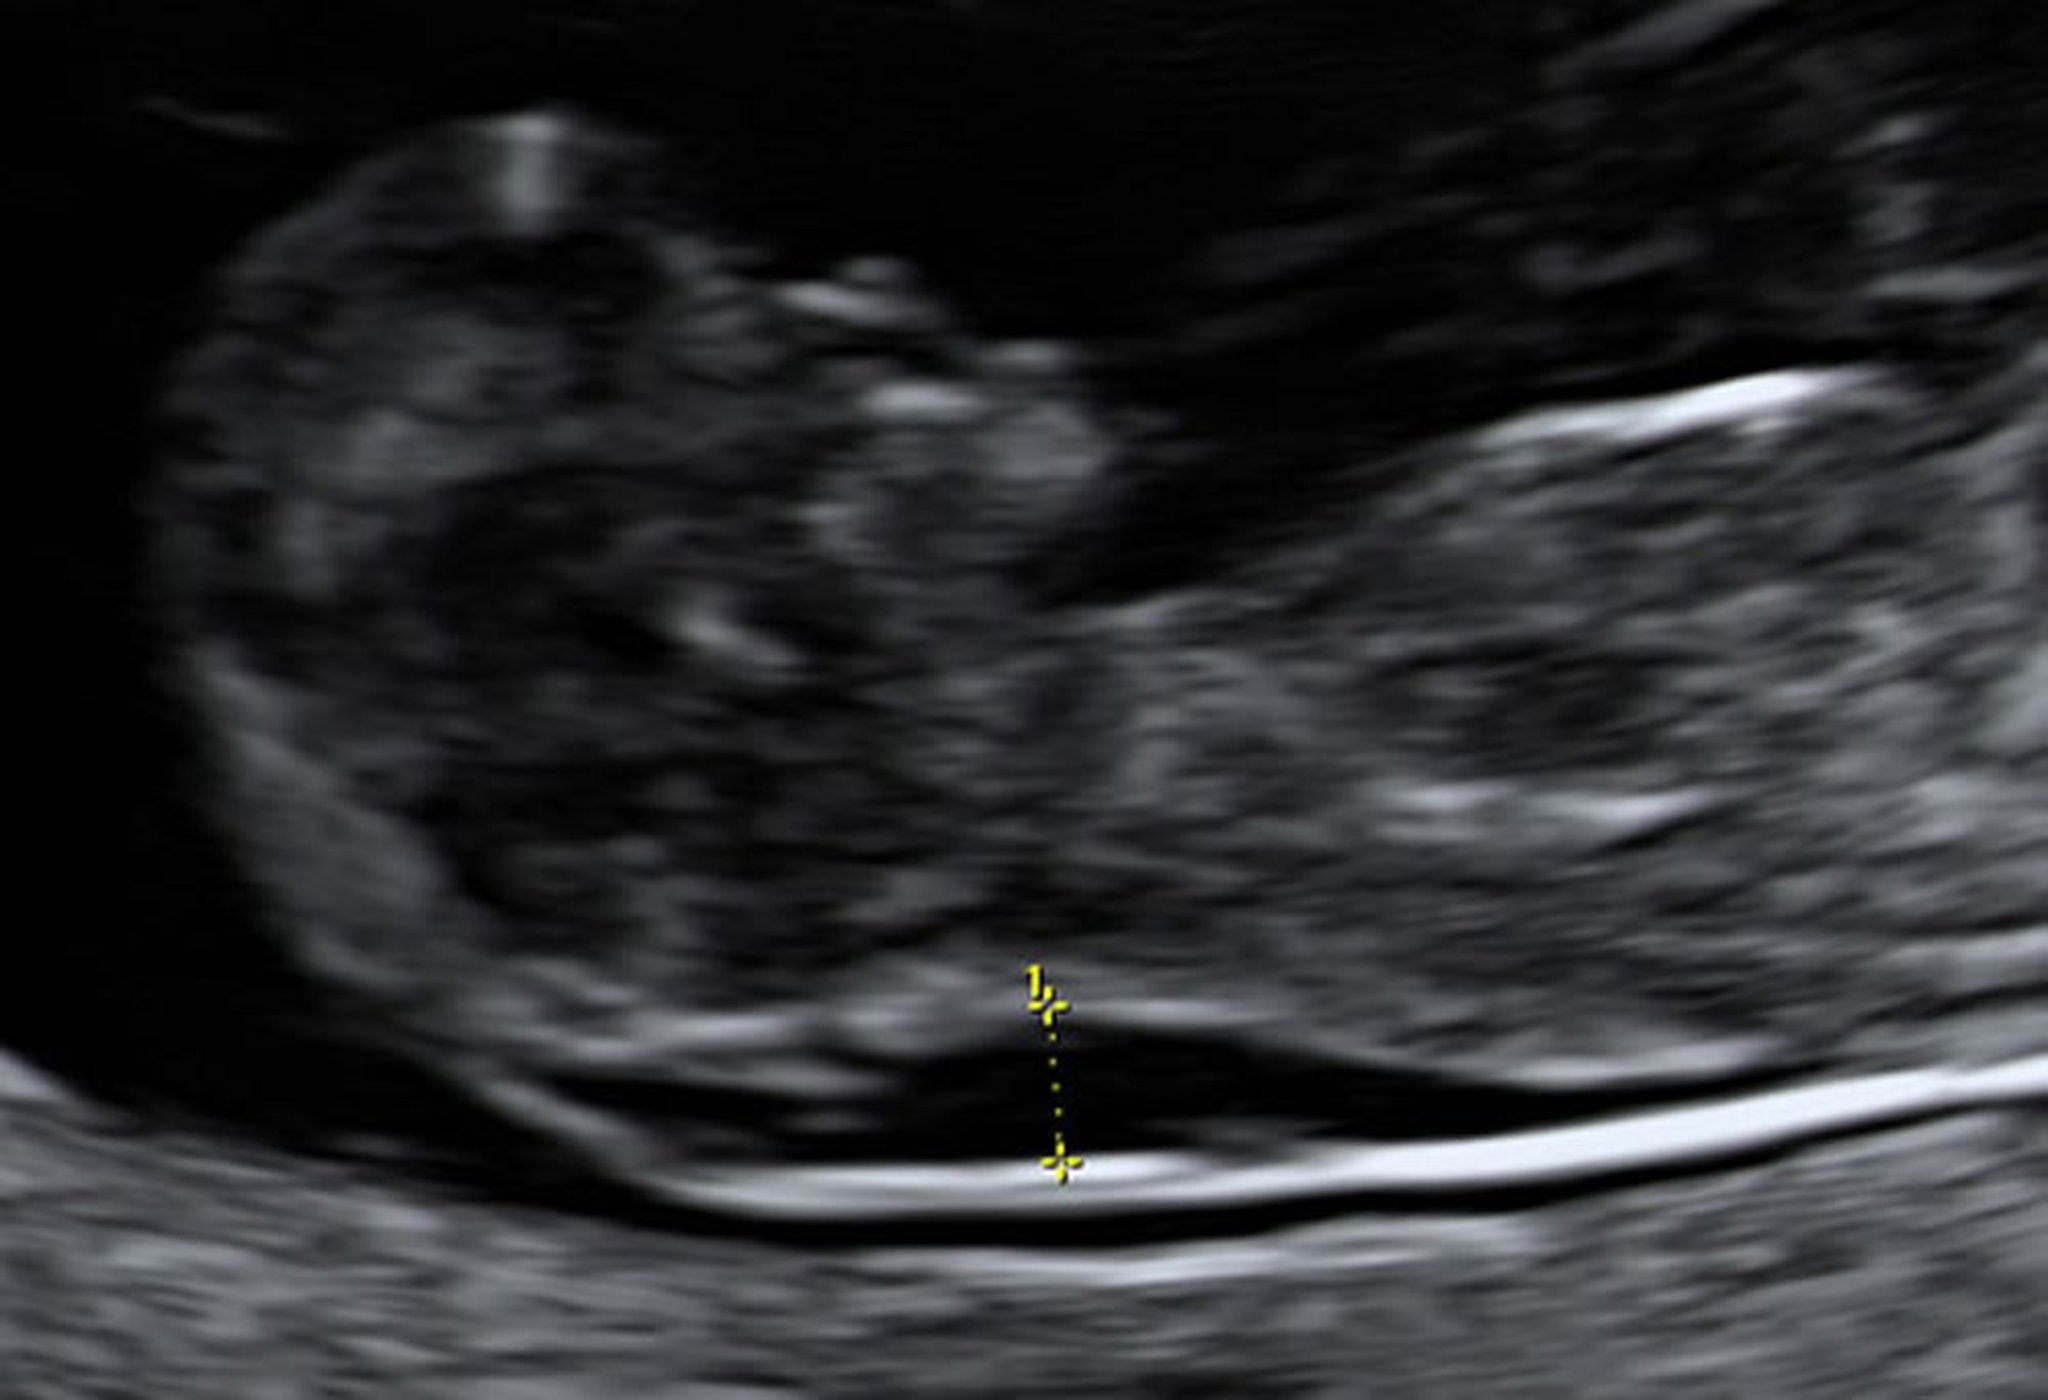

Ультразвуковое исследование показывает увеличение затылочной полупрозрачности плода на 10-й неделе

Биопсия ворсин хориона указала, что этот плод имел синдром Дауна.

Photo from Jeffrey S. Dungan, MD.